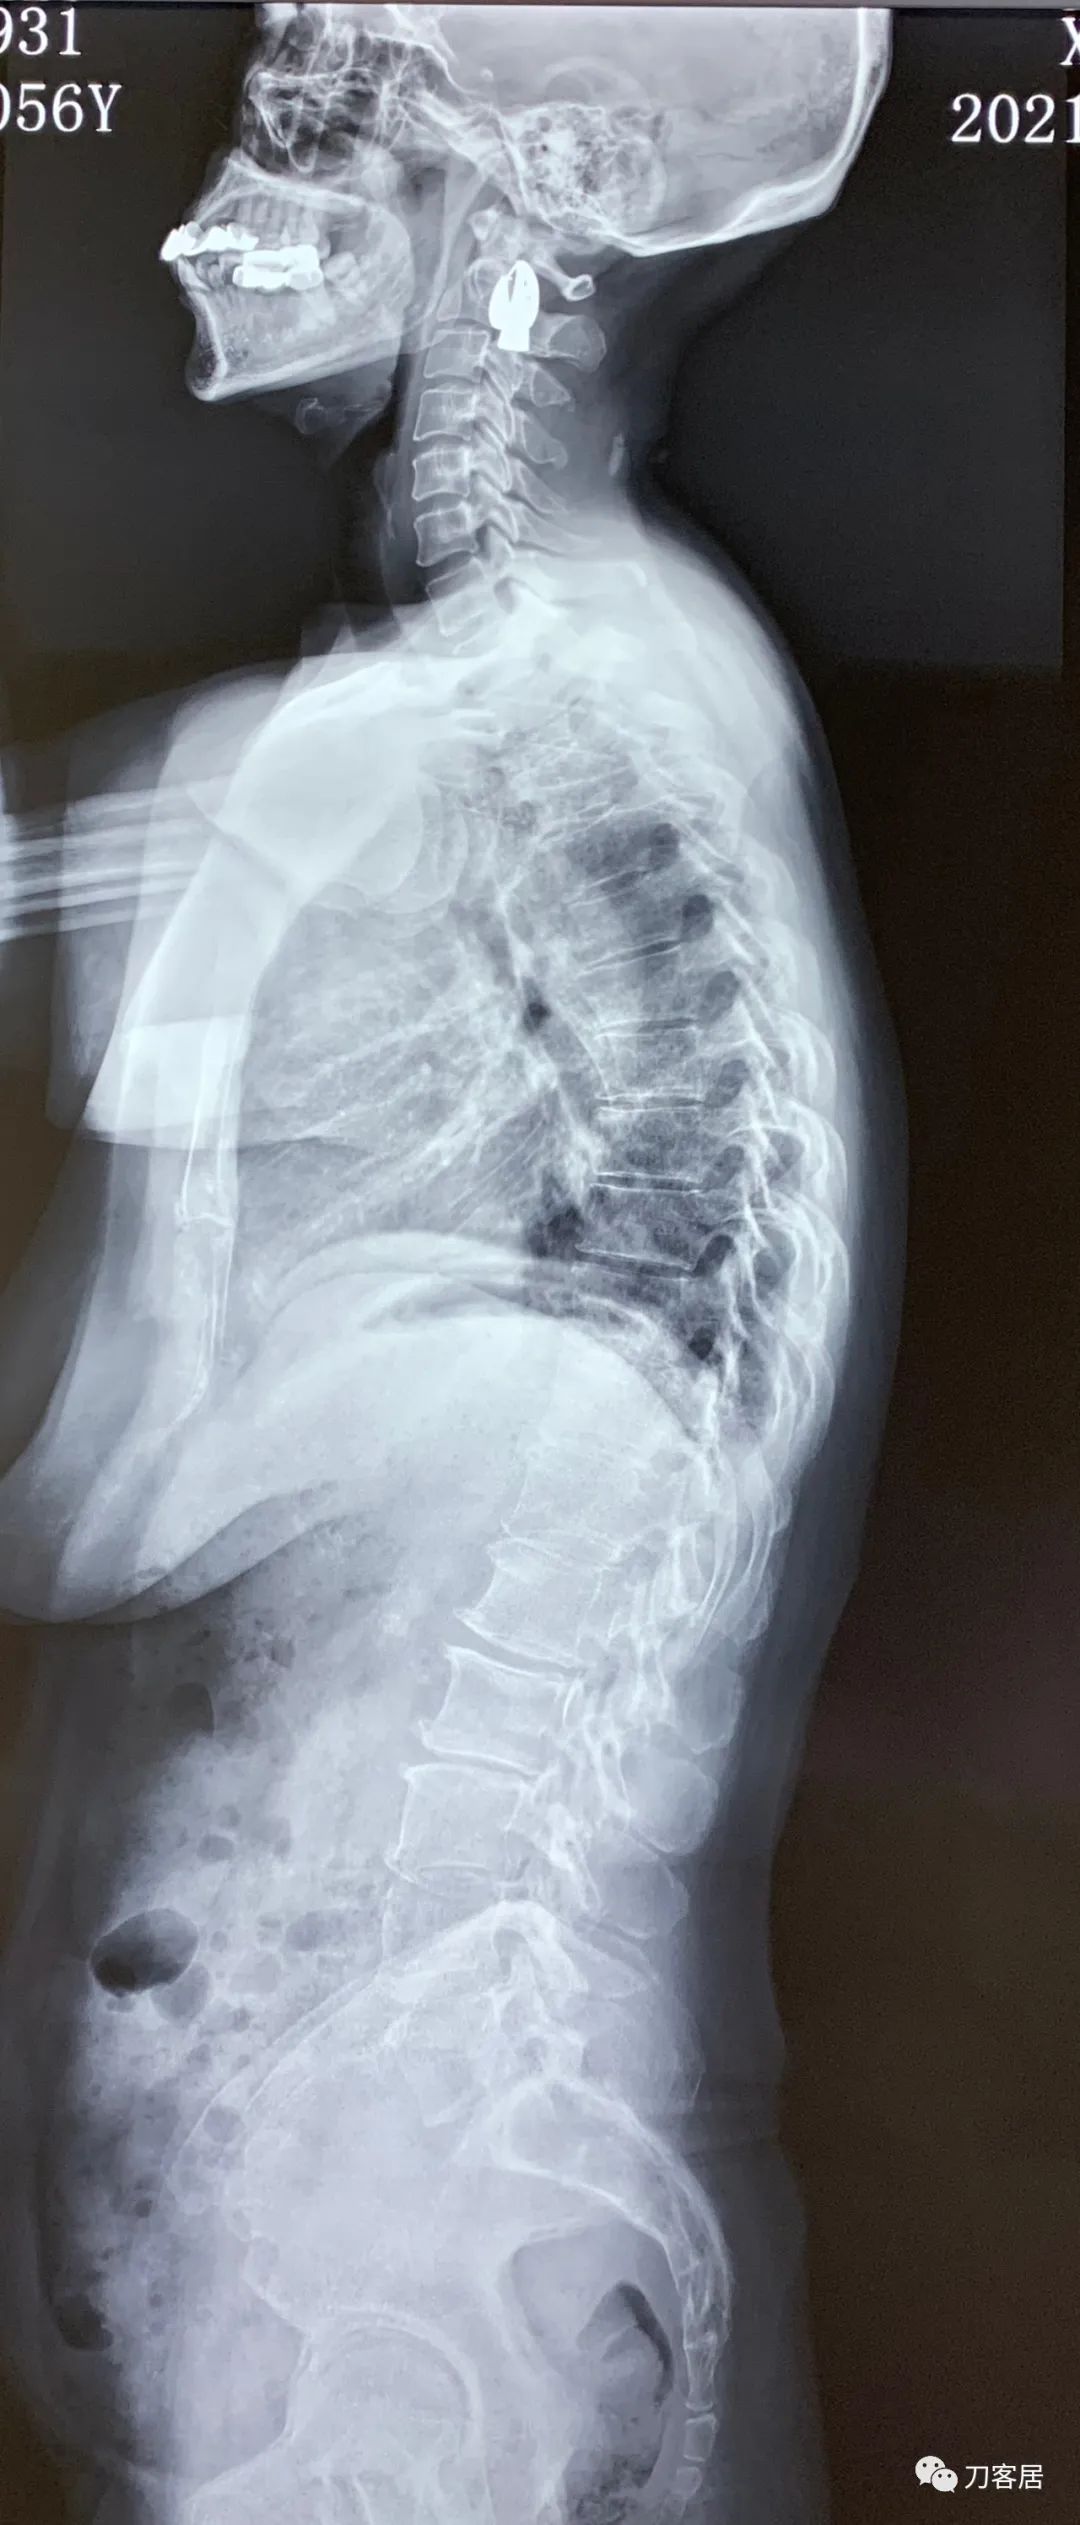

建议其查双光子骨密度,骨盆正位片以及腰椎间盘平扫。腰椎正侧位X线片以及动力位片,站立位脊柱全长正侧位X线片,以了解其是否有骨质疏松,并了解脊柱侧弯情况,腰椎局部X线表现情况和腰椎间盘突出和椎管狭窄情况。

从这个患者的影像资料分析,颈椎间盘突出问题不大,没有明确的上位神经元损伤表现,所以,不考虑颈椎和胸椎问题。腰椎侧弯畸形,但不严重。因为存在腰椎侧弯,使得腰椎MRI在扫描切面的时候,显示的椎间盘突出或椎管狭窄会有一定的误差,所以,又加做了经椎间盘的CT平扫,影像表现并不严重,综上,腰椎间盘突出,腰椎管狭窄,腰椎侧弯,不考虑手术治疗。同时,患者的主要痛苦是心理疾病,而不是器质性疾病,所以,以心身疾病治疗为主。虽然患者骨密度检查结果提示正常,但X线片显示骨质疏松,且其症状也与骨质疏松的症状有符合之处,比如静息痛,不能入睡,动作及姿势变换时痛加重等,所以,给予实验性抗骨质疏松治疗,以观疗效。